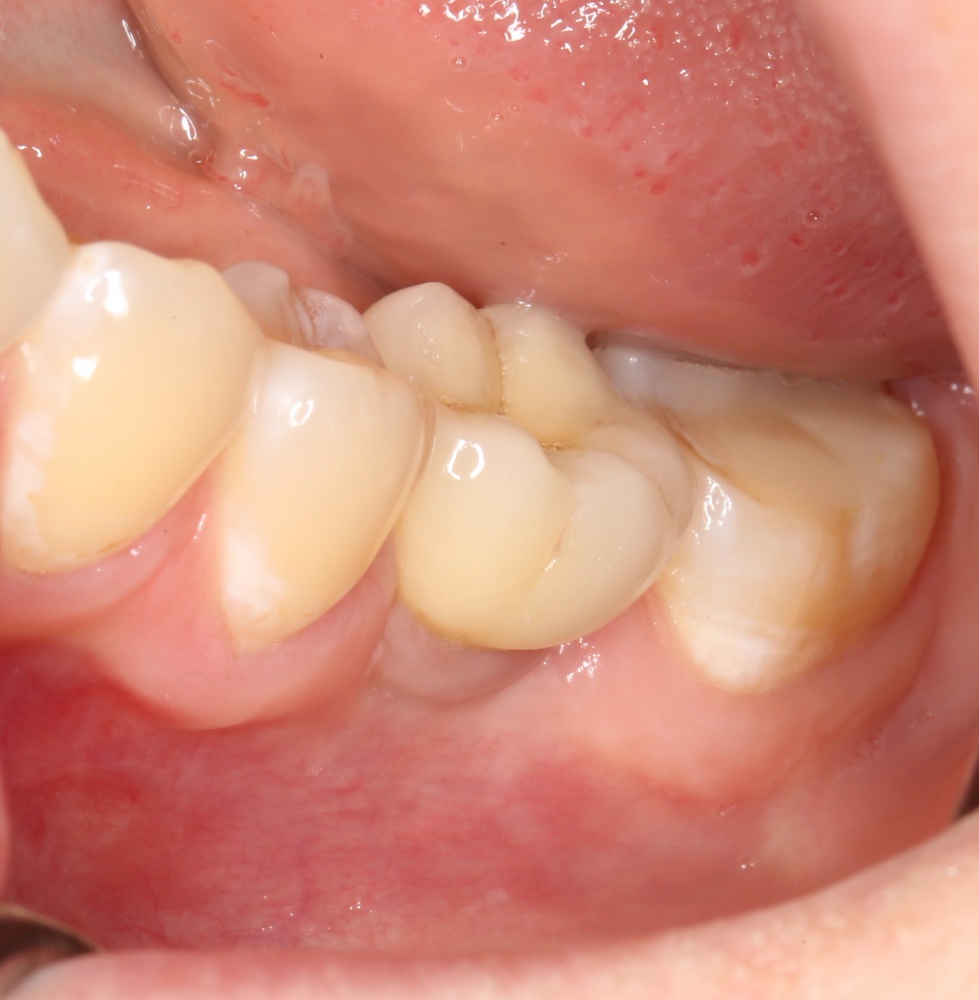

Рекомендации по установке имплантов. Для всех. Часть II.